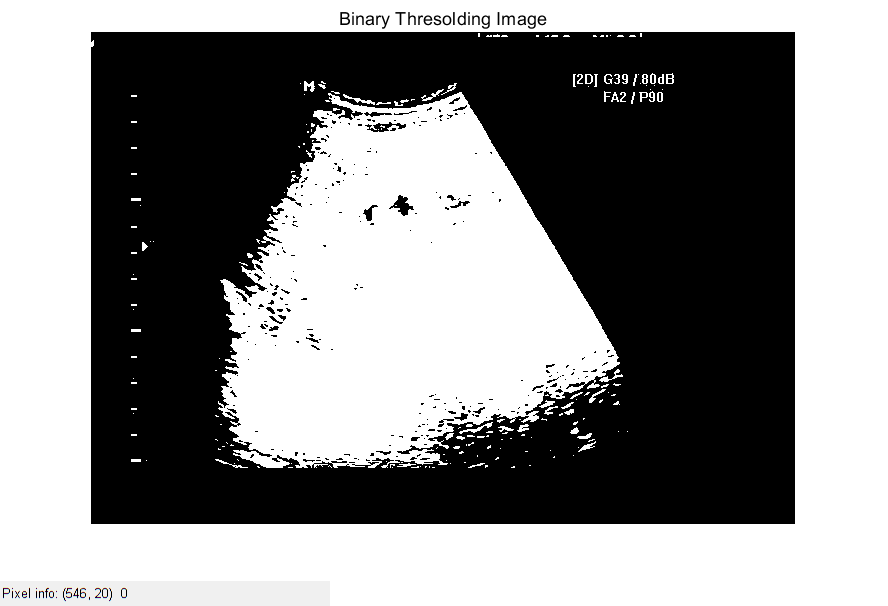

%% Thresolding using 20 intensity value, above 20 pixel value 1 or 0

binary_image=imbinarize(gray_image,20/255); %Otherwise Binary image or c = b>20; %divide by 255 because imbinarize

%function accepts values between 1 and 0

figure;

imshow(binary_image),title('Binary Thresolding Image');

impixelinfo